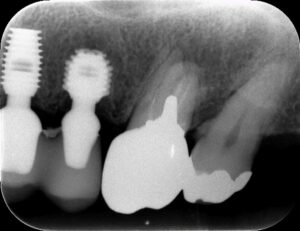

厚みが9mm以上あれば、通常の方法でインプラントが可能です。こんな感じです。

こういう感じが理想ですね。しかし、いつも理想的ではありません。